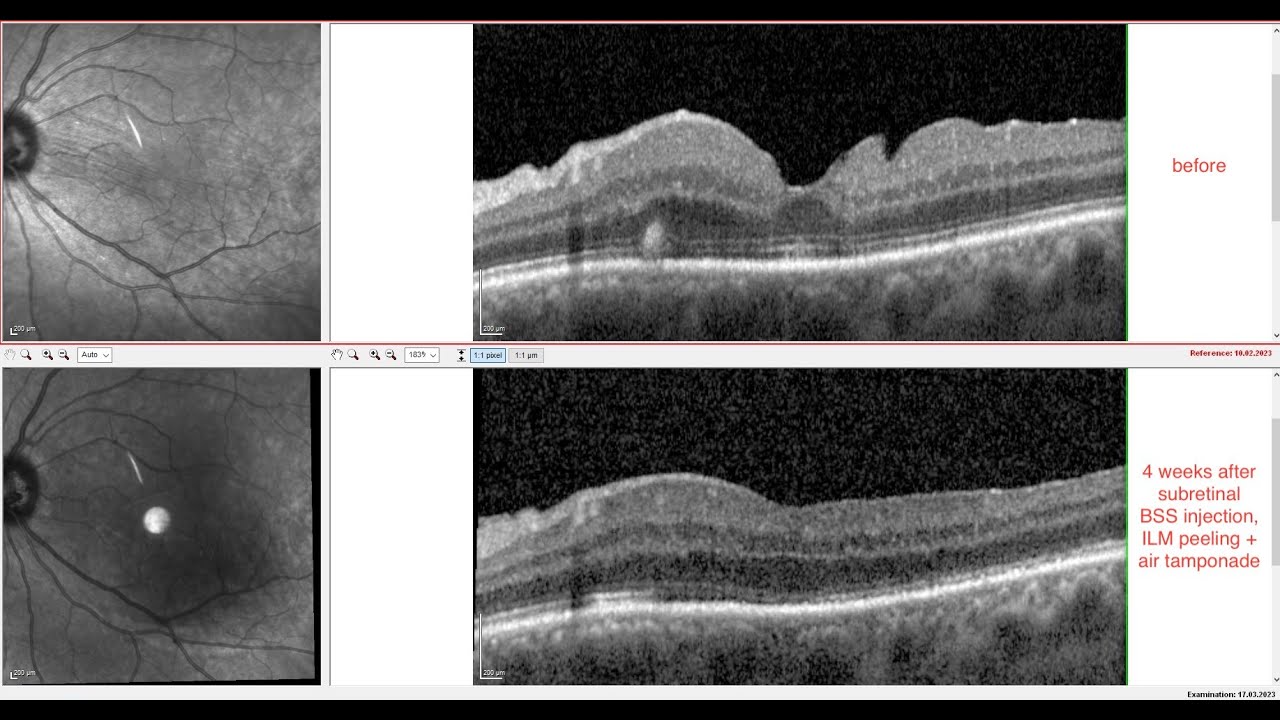

From www.reddit.com